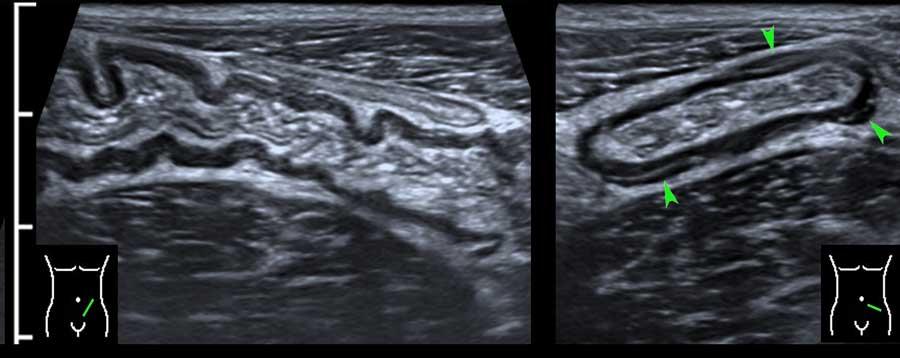

Ruột non được gắn vào mạc treo ruột, được gấp lại như hình chiếc quạt.

Mạc treo chứa một lượng mỡ thay đổi, và mạc treo có mỡ bị gấp nếp tạo ra hình ảnh nhiều lớp, đặc biệt khi bị nén ép trong quá trình siêu âm.

Mạc treo bình thường (mũi tên) ở những bệnh nhân gầy chỉ có thể nhìn thấy khi có cổ trướng.

Ở người béo phì, mạc treo chứa nhiều mỡ và có thể được quan sát như một cấu trúc nhiều lớp, dẹt, dễ nén ép.

Trong một mặt phẳng, điều này có thể mô phỏng hình ảnh thành ruột dày lên (các mũi tên trong hình bên trái).

Xoay đầu dò 90 độ (hình bên phải), cấu trúc này ngay lập tức được nhận ra là một cấu trúc phẳng (các mũi tên).

Ở rìa mạc treo mỡ, có thể quan sát thấy nhu động rõ rệt ở hai quai ruột non.